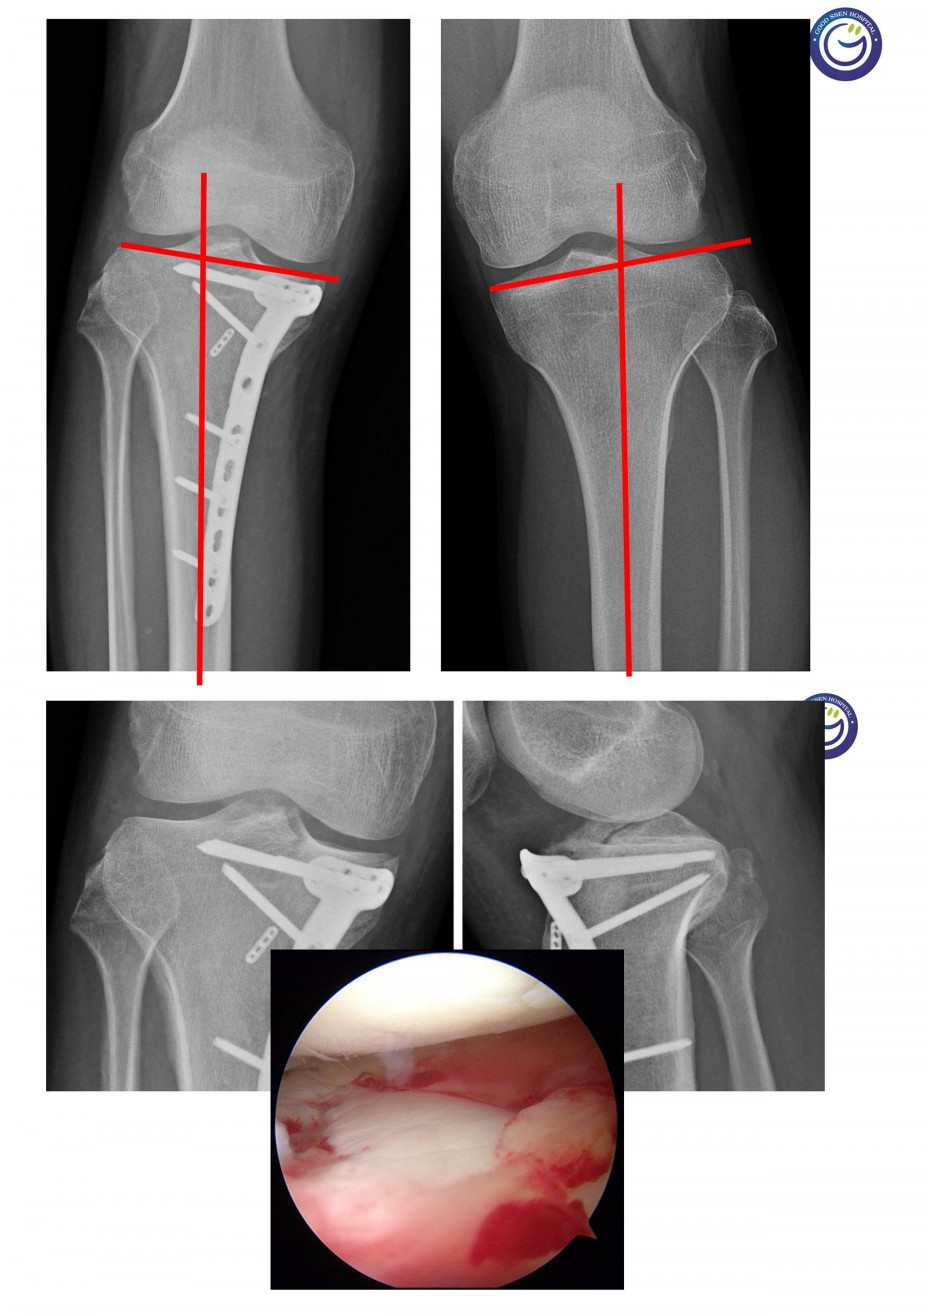

관절을 침범하는 심한 분쇄골절